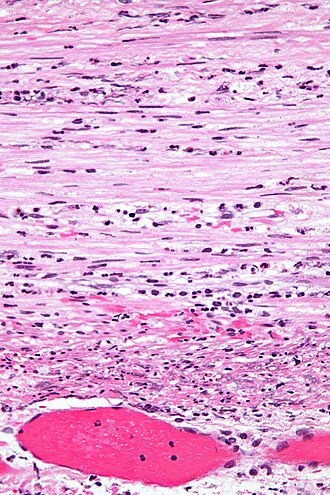

Template:Px Acute appendicitis. H&E stain. | |

| LM | neutrophils in the muscularis propria |

- Neutrophils in the muscularis propria - key feature.

- Appendicitis - low mag.jpg

Appendicitis - low mag. (WC/Nephron)